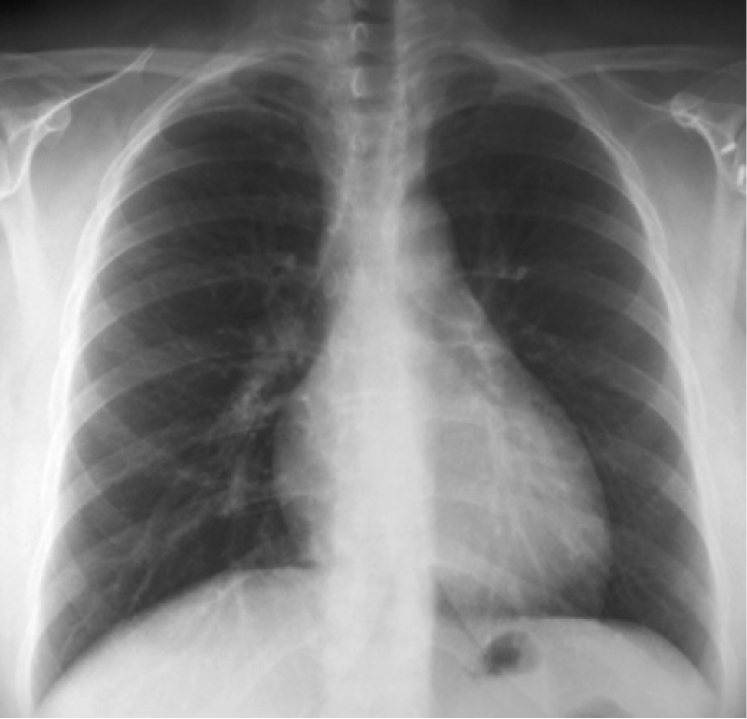

Figure 3: Heart size projection in Postero-Anterior (PA) vs Antero-Posterior (AP). The projection of the heart (red silhouette) illustrates that anatomical ratios depend on the plane distance to the x-ray source.

The projection information is highly relevant for diagnosis. For example, AP views, which are commonly used in pediatric patients, show an enlarged heart silhouette (Fig. 2(j)) that should not be interpreted as cardiomegaly, but merely the expected large-depth ratio of reversed organ observation (Fig. 3). Another illustrative example is the distinct pattern that pleural effusions have in the standing position (Fig. 4(a)), in which a typical meniscus sign is commonly found as opposed to decubit projections (Fig. 4(b)). Given that the number of different projections is unbalanced (for instance, PA followed by lateral projections typically comprise the majority of chest x-rays), there is the risk that none of the other projections will have sufficient instances with which to train models capable of discriminating pathological from non-pathological patterns in the context of the projection.

There are particular radiological landmarks that differentiate projections, which radiologists are trained to identify. For instance, in the case of PA projections, these landmarks are the presence of air in the gastric chamber and the scapulae projected outside the lung fields. Although these features can be learned, models trained in unbalanced datasets with a poor representation for different projections may not have sufficient instances to properly learn those patterns. An illustrative example is when the heart enlargement in AP projections is attributable only to the effect of the projection, while the trained model erroneously predicts cardiomegaly.